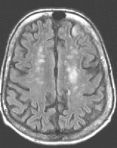

In the brain, it is used to determine hyperacute and acute strokes (detectable from minutes to days). Conventional imaging may not be able to detect hyperacute strokes or differentiate acute from chronic infarcts. With MR diffusion, detection of acute infarcts is immediate and differentiation from old infarcts is obvious.

Routine FLAIR MRI images (left) cannot differentiate between acute infarcts and chronic ischemic changes/infarcts. The diffusion MRI (right) clearly demonstrates an acute infarct in the left frontoparietal region (the chronic changes do not "light up" on the diffusion study).